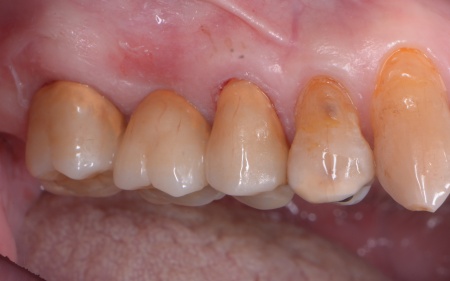

神経が温存できていることを確認できたため精密な型取りを行い、虫歯の再発リスクが低く強度も高いセラミックのジルコニアでブリッジを新たに作製しました。

完成したブリッジを装着し、痛みや違和感がなく噛み合わせや見た目にも問題がないことを確認して、治療を終了しました。